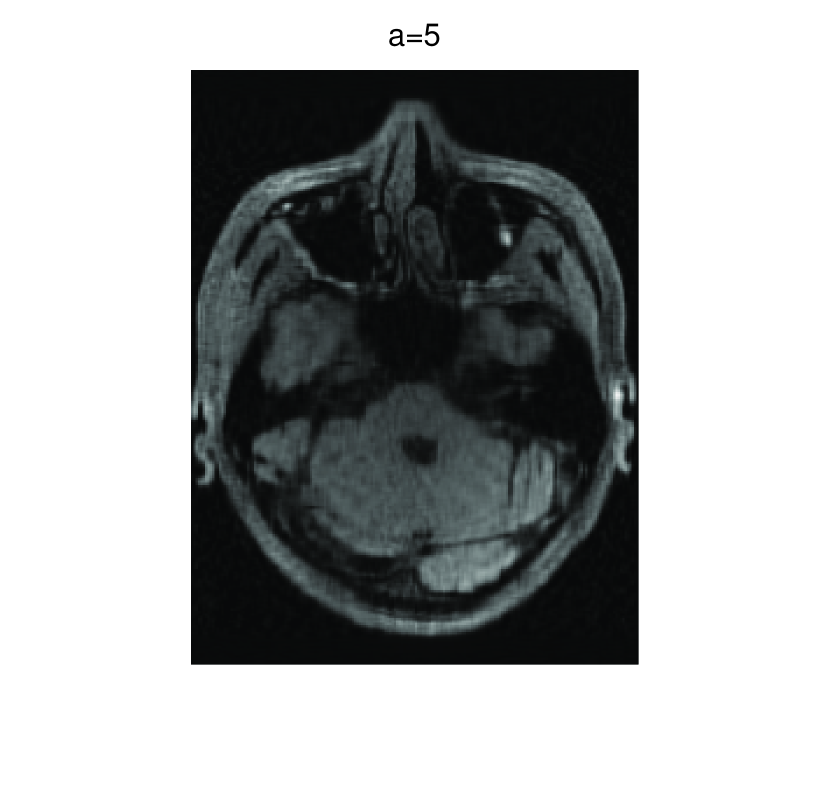

In this subsection, we demonstrate performances of ISVTA on image inpainting problems. The ISVTA is tested on some medical grace images ( Brain angiography image (BAI), Hand angiography image (HAI) and Intracranial venous image (IVI)). We use the SVD to obtain their approximated low-rank images with rank , respectively. Numerical results of ISVTA for theses low-rank image inpainting problems are reported in Table 5, 6, 7, 8.

Table 5, 6 show that ISVTA performs powerful in finding a low-rank matrix on image inpainting problems. Indeed, we could get an exact low-rank image by the ISVTA by choosing proper . Moreover, it is necessary to point out that our method does not work well for all , and we can find that is not a good strategy for the low-rank IVI either or . The numerical results of ISVT, SVTA and SVPA compared in Table 5, 6, 7, 8, 9, 10 under same circumstance show that the ISVT algorithm performs far more better than ISTA and SVPA on image inpainting problems for some proper .